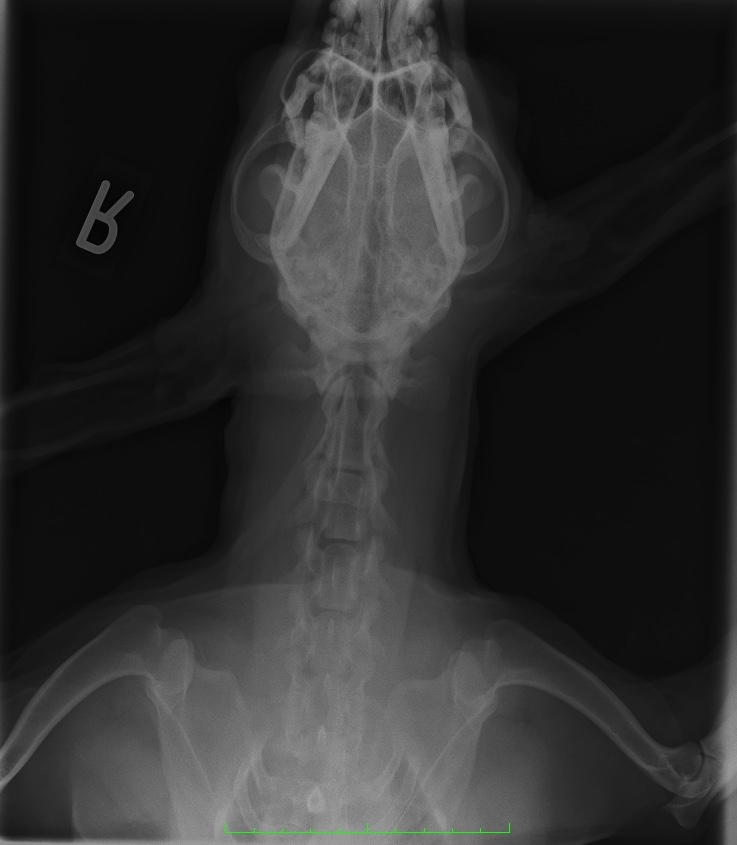

レントゲン検査

レントゲン検査は耳鏡やオトスコープが入らないくらい耳の穴が塞がっているときなどに実施します。

耳の内部が物理的に観察出来ない場合は、レントゲン検査で耳の中に液体がたまっているかどうかや耳の中に石灰が沈着していないか、腫瘍で耳が塞がっている可能性がないかなどが確認できます。

耳の症状が長引くと、耳の穴が閉じてしまってレントゲン検査でないと観察できないことがあるのですね。

耳のトラブルは早めに動物病院にご相談にいらしてください。